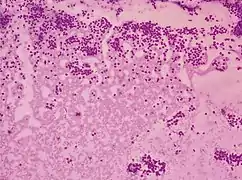

Thyroid cytopathology of Bethesda category III with clotting artifact